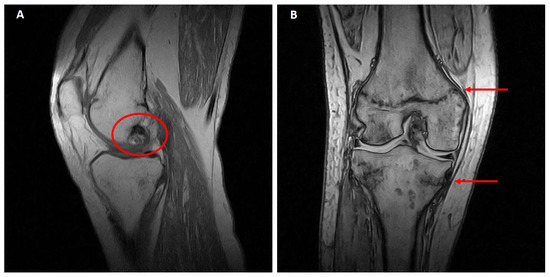

One year later, an MRI investigation showed an initial osteonecrotic area in the right knee and trabecular metaphyseal fractures of the distal femur and proximal tibia (Figure 2A,B), as well as healed distal tibial and ankle stress fractures (not shown).

Figure 2. Right knee MRI (July 2016). (A) Osteonecrotic area of about 2 cm in the external femoral condyle. (B) The arrows indicate femoral and tibial metaphyseal fractures.